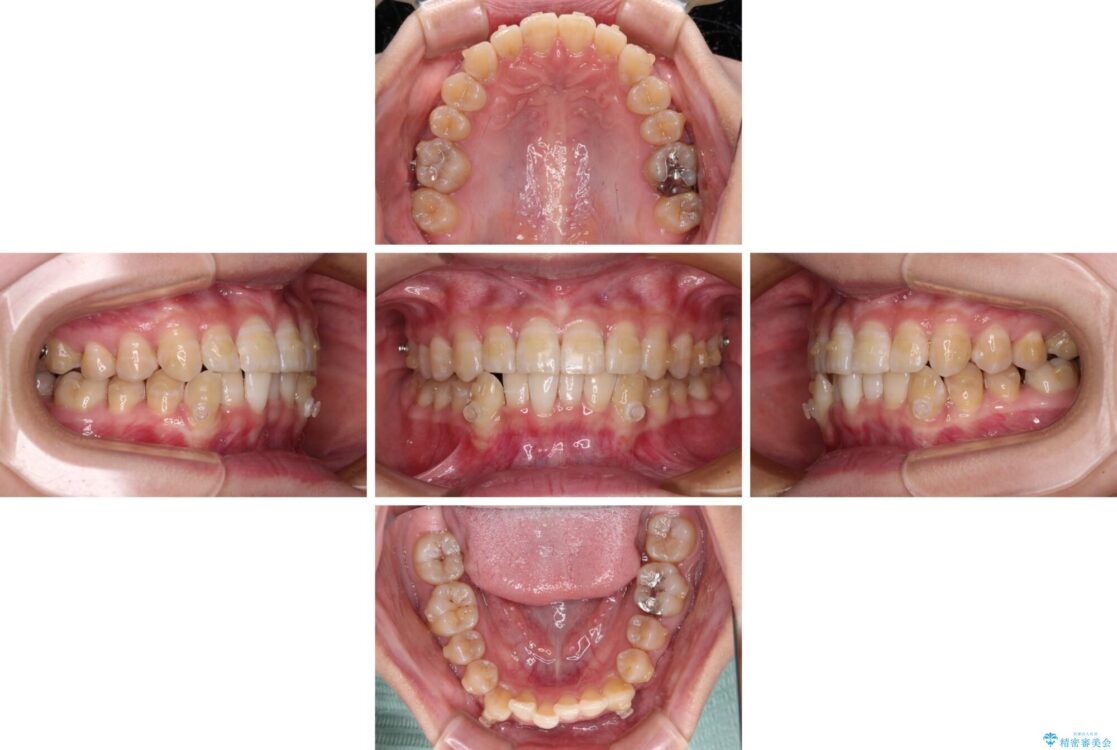

下顎の八重歯を気にして来院された患者様です。

下顎前歯にデコボコが集中していたため、顎間ゴムによる後方移動とIPR(歯と歯の間を削ること)により歯列を整えることとしました。

治療前、下顎前歯のデコボコが集中しており、奥歯の咬み合わせは、上顎に対して下顎が前方位にある状態でした。下顎の歯列を後方へ移動させる治療はインビザラインの得意とするところですので、1年程度で無事に治療を終えることができました。

治療前

• 【モニター】下顎前歯のデコボコをインビザラインできれいに 治療前画像